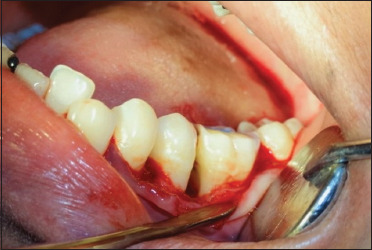

伴有口腔脱屑性病变的系统性红斑狼疮(SLE)是罕见的临床病例之一。牙周病和系统性红斑狼疮的发病机制多种多样,病理特征也各不相同。牙周炎和自身免疫性疾病的组织破坏机制具有相似的途径,越来越多的报道研究了这两种疾病之间的关联。本病例是一名 24 岁的女性患者,主诉牙间隙普遍增宽。同时,她还伴有脱发、虚弱、腿部水肿和关节痛。根据美国风湿病协会和欧洲皮肤病与性病学学会的标准,该患者在来看牙医的一年前被确认患有系统性红斑狼疮。她患有脱发、乏力、关节痛和腿部水肿。根据口腔、临床和影像学检查结果,她被诊断为侵袭性牙周炎病例。经过非手术牙周治疗,翻瓣,清创,用四环素进行根部调理后,在所有有角骨缺失的部位植入牛骨异种移植,然后用 4-0 丝线间断直接环形缝合技术缝合。每 6 周进行一次临床和影像学评估,以检查治疗的进展情况。6 个月和 8 年的随访结果显示,临床和影像学效果令人满意。根据本病例报告和以往的文献,我们推荐使用异种牙移植治疗侵袭性牙周炎患者。

Systemic lupus erythematosus (SLE) with oral desquamative lesions is one of the rare clinical entities. Periodontal disease and SLE display various mechanisms and possess a wide range of pathological characteristics. The tissue destruction mechanism of periodontitis and autoimmune diseases share similar pathways, and mounting reports studied the association between these two entities. The present case is of a 24-year-old female patient who complained of generalized widening of spaces in between the teeth. Along with it, She suffered from loss of hair, weakness, edema in the legs as well as arthralgia. The patient was identified to be suffering from SLE according to the American Rheumatism Association and European Academy of Dermatology and Venereology criteria 1 year before she reported to the dentist. She suffered from hair loss, weakness, arthralgia as well as edema in the legs. Based on the oral, clinical, and radiographic findings, she was diagnosed with aggressive periodontitis case. After nonsurgical periodontal treatment, the flap was reflected, debridement was done, after root conditioning with tetracycline, bovine osseous xenograft was placed in all the sites where ever there is angular bone loss, later sutured with interrupted direct loop suturing technique with 4-0 silk suture. Clinical and radiographic evaluation was done every 6 weeks to check the progress of the treatment. 6 months and 8-year follow-up revealed satisfactory clinical and radiographic outcomes. Based on the present case report and the previous literature, we recommend the use of xenograft in treating aggressive periodontitis patients.